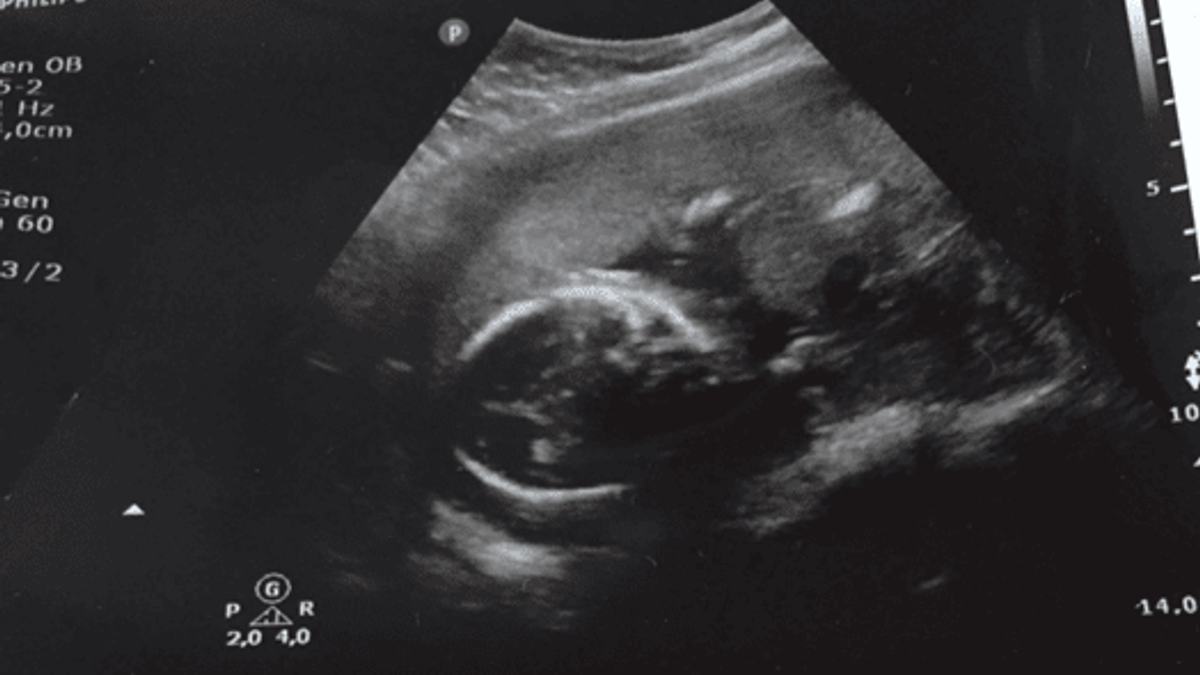

Gelukkig kenden ze onze situatie en ook de overstimulatie van de afgelopen weken (het ging gelukkig steeds beter met mijn vocht in de buik). Ze gingen direct een echo maken, het hartje werd gezocht en het was overduidelijk aan het bewegen. Dolgelukkig waren we op dat moment. Bij Jules stroomde de tranen over zijn wangen. Eindelijk we zijn zwanger en het hartje klopt. Wat hebben we hier lang op gewacht, maar ondanks de overstimulatie, de trajecten, de jaren, de tegenslagen, was het dit allemaal waard! Onze grootste wens kwam uit, we gaan papa en mama worden in oktober 2016.

Op 15 maart hadden we de eerste echo bij onze verloskundig. Het zag er goed uit. Met mijn fysieke gesteldheid ging het niet zoals het zou moeten zijn, maar door de zwangerschap nam ik alles voor lief. Ik heb weken overgegeven, liep bij de osteopaat vanwege ischias. Maar het maakt allemaal niet uit, ik heb alles over voor onze Joeks/Joeksie (onze projectnaam). In de meivakantie gingen we samen op vakantie naar Ibiza. De rust had me goed gedaan, ik had geen last meer van Ischias of overgeven. Nu kon het genieten van mijn zwangerschap echt beginnen.

Op 3 mei gingen we samen met mijn zusje naar de echopraktijk om te kijken of ons wondertje een Joeks of een Joeksie was. Het was lastig om te zien in eerste instantie, want het was maar aan het bewegen en zich druk aan het maken. Uiteindelijk heeft ze zich laten zien. We krijgen een dochter.

Op 16 mei kregen we de schrik van ons leven, ik begon te vloeien. We hebben direct de verloskundige gebeld, we mochten meteen langskomen. Ze zag op de echo dat het hartje klopte. Er viel een last van ons af, maar we moesten voor de zekerheid nog even langs het ziekenhuis. In het ziekenhuis hebben ze nog beter gekeken en zagen ze niets verontrustends. Het zou wellicht kunnen liggen aan de placenta die erg laag voor de uitgang lag. We moesten het goed in de gaten houden. Als ik toen eens wist wat ons allemaal nog te wachten stond…